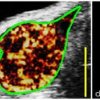

Ultrasound DCE-PI is a method used to non-invasively monitor the blood flow in the microcirculation. Since growing tumors require abnormally increased blood flow, changes in blood vessel structure or density can provide information regarding tumor malignancy.

The team used a drug that inhibits a protein specific to tumors. They then used the imaging tools to measure the response of two different tumors, one known to respond to the drug therapy, and a second known not to respond. The results indicated that USMI was able to detect molecular signs of tumor response to therapy after only 2 days. A change in blood flow in the tumor was observed to detect response after day 14 using DCE-PI. Over the same period, standard volume measurements were not able to detect therapeutic response, and prior studies suggested that volume measurements do not become indicative of response until approximately 28 days. Thus, these methods showed a notable improvement in the early identification of tumor response to therapy, using contrast enhanced ultrasound imaging.